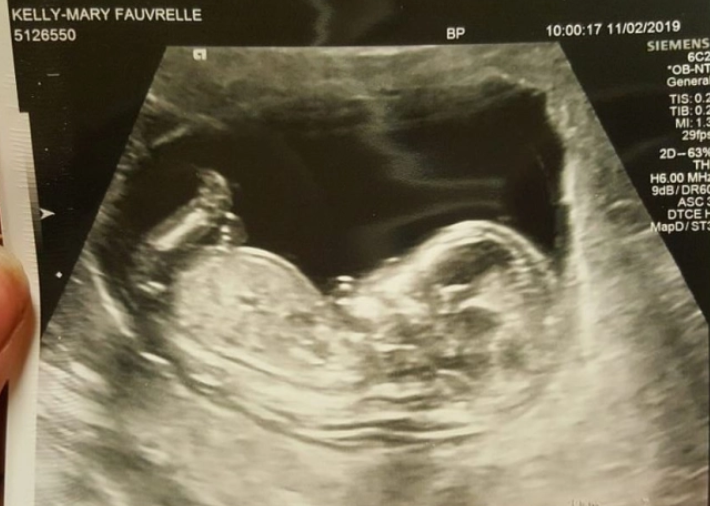

本文图片

凯莉被害时已怀孕33周